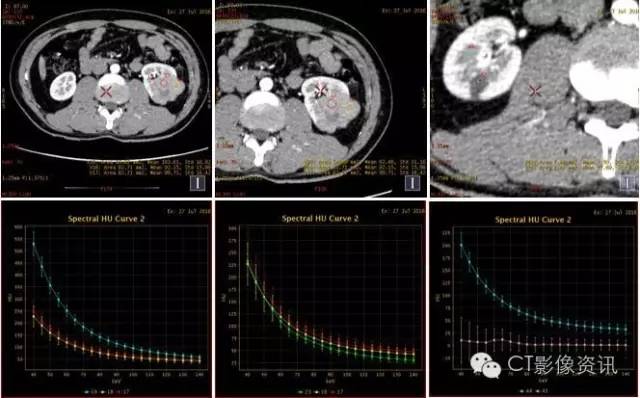

能谱曲线分析

左肾病变与左肾髓质具有较一致的同源性关系;右肾病灶呈“勺”状曲线,且与左肾病灶及肾皮质、髓质存在明显差异。

左肾病灶与左肾实质存在差异;右肾病变依然呈“勺”状曲线。

此病例为年轻男性,体检时发现双肾病变。进行CT平扫及GSI增强扫描,从病变位置、形状、增强特点可考虑左右肾为不同病变。进行能谱数据进一步分析发现,左肾病变基物质碘含量及能谱曲线与左肾髓质相似(皮质期明显),右肾病变基物质碘含量及能谱曲线与肾实质及左肾病变存在较大差异,并且右肾病变在三期增强扫描能谱曲线均为“勺”状,提示其中含有脂肪成分。综合以上参数考虑,左肾病变与左肾髓质关系密切,右肾病变含脂肪成分,趋向于错构瘤。基本排除左右肾病变为同一病变。